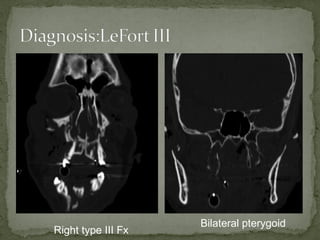

A 38-year-old man was found unconscious 40 yards from the scene of a motorcycle accident. He had obvious facial trauma including a midface fracture, severe facial edema, and blood in his oropharynx. His vital signs included a temperature of 98.6 F, heart rate of 120, respiratory rate of 12, and oxygen saturation of 90% on a nasal cannula with a blood pressure of 95/60. His Glasgow Coma Scale was 8. Imaging showed right type III and bilateral pterygoid fractures. He required intubation, ophthalmology consultation, and admission to the operating room for open reduction and internal fixation of his facial fractures.